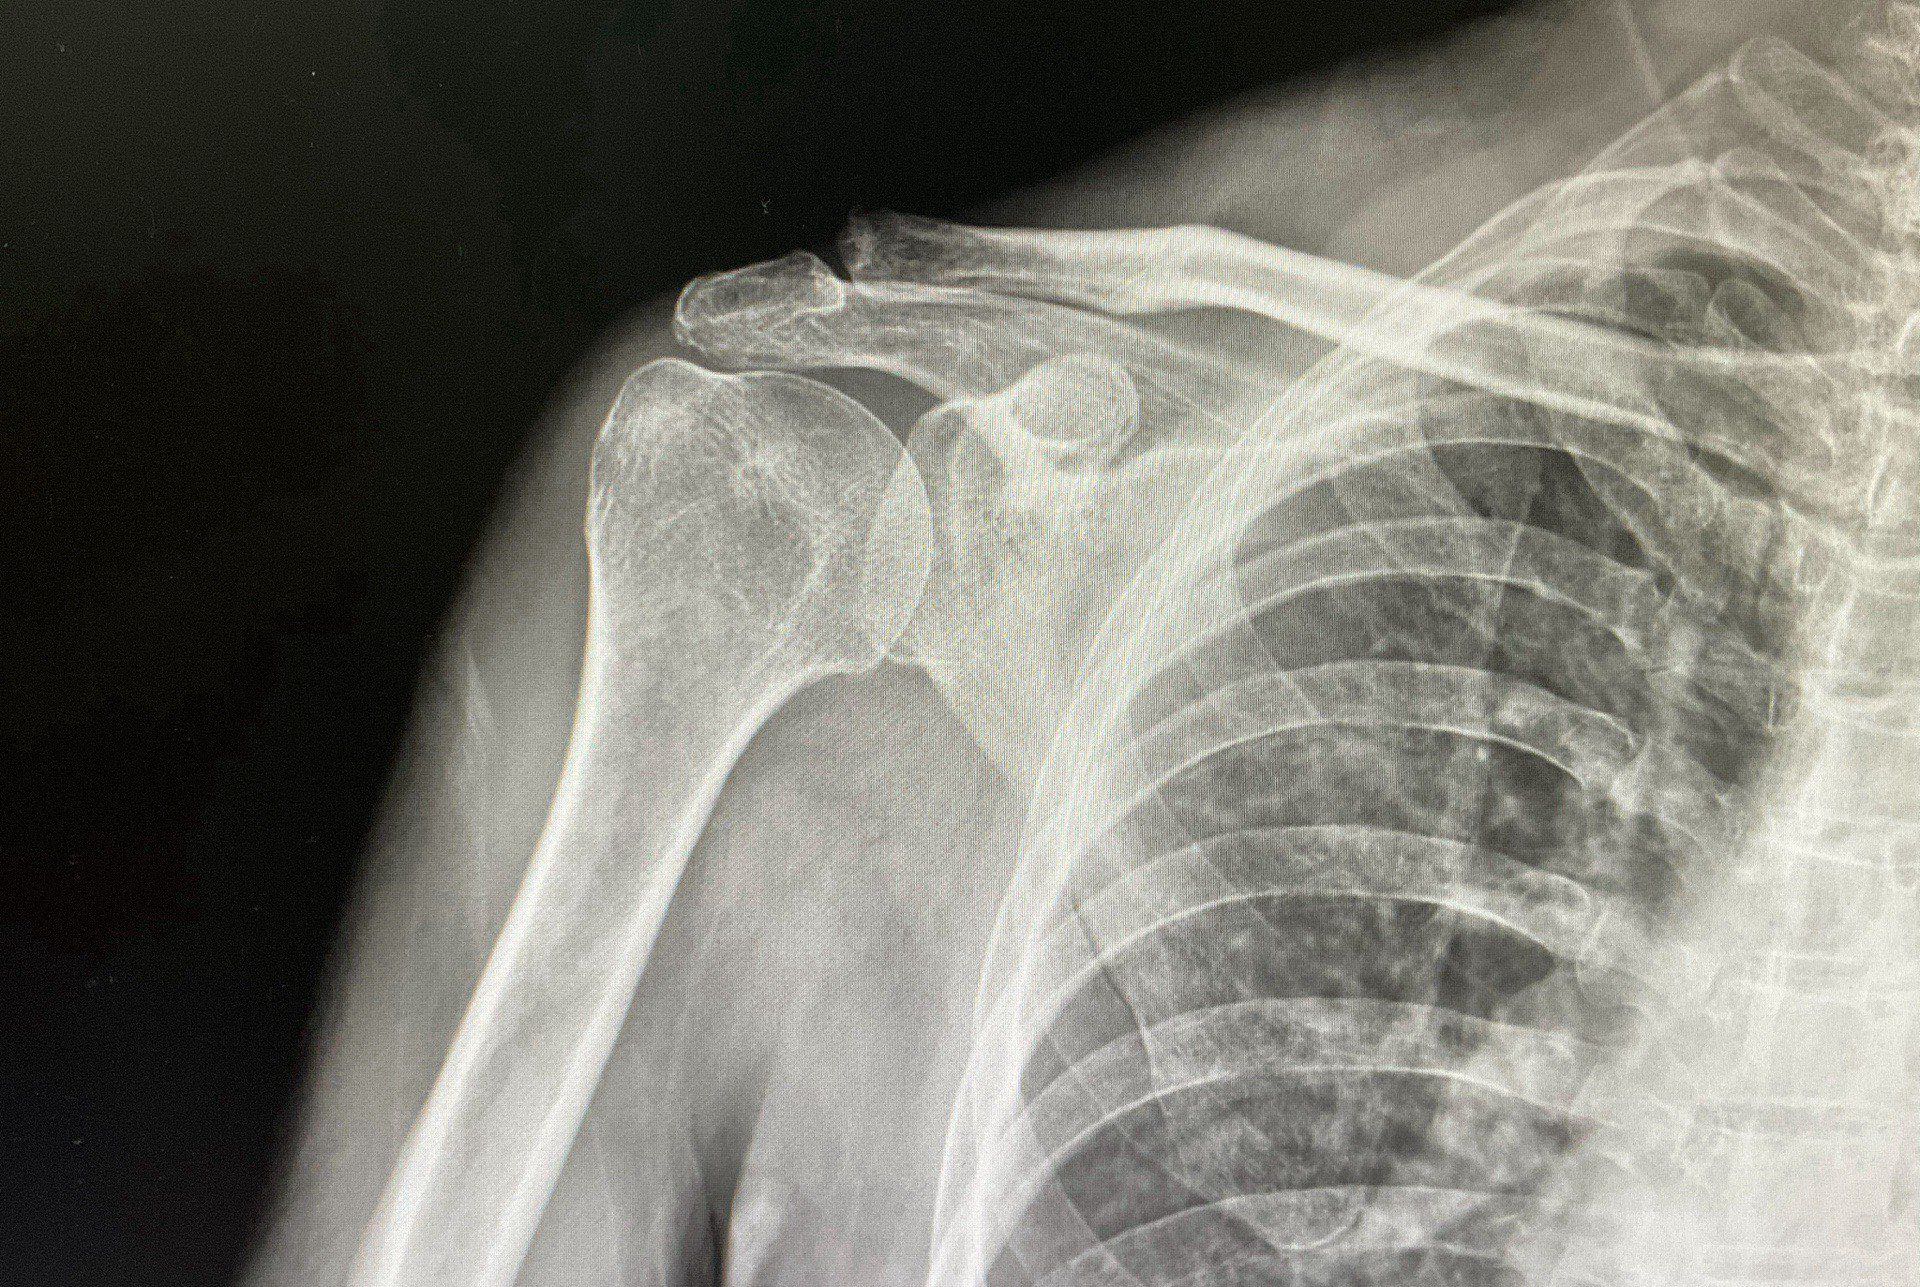

หากคุณรู้สึกปวดไหล่จนถึงขั้นทำกิจวัตรประจำวันลำบาก เช่น การยกแขน นอนหลับ หรือทำงาน และอาการไม่ดีขึ้นแม้พักผ่อนหรือใช้ยาบรรเทาปวด อาจเป็นสัญญาณของ การบาดเจ็บรุนแรง เช่น เอ็นไหล่ฉีกขาด หรือการอักเสบเรื้อรัง ที่ควรได้รับการตรวจวินิจฉัยอย่างละเอียด

หากคุณพบว่าแขนไม่มีแรง ยกแขนไม่ขึ้น หรือรู้สึกว่าแขนทำงานไม่เต็มที่ อาจเกิดจากการ กล้ามเนื้อเอ็นไหล่ฉีกขาด หรือ เส้นประสาทถูกกดทับ ซึ่งถ้าไม่รับการรักษาทันท่วงที อาการอาจแย่ลงและส่งผลกระทบต่อการใช้งานไหล่ในระยะยาว

หากคุณได้ยินเสียงกร๊อบหรือกึ๊กขณะเคลื่อนไหวไหล่ และรู้สึกเจ็บหลังจากนั้น อาจเป็นสัญญาณของ การบาดเจ็บในข้อไหล่หรือกระดูก ซึ่งจำเป็นต้องตรวจเพิ่มเติม เช่น การตรวจด้วย Ultrasound หรือ MRI เพื่อดูว่าเกิดความเสียหายที่จุดใด